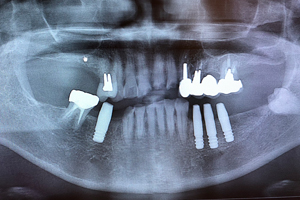

治療前

治療後

- 年齢・性別

- 60歳

- 治療期間

- 6ヶ月

- 抜歯

- 残根抜歯のみ

- 治療費

- 184.8万円

- 備考

- 右上5.6 右下5 左下4.5.6欠損

- 治療内容

- 6本のインプラントを右左側に2回に分けて埋入

- 施術の副作用(リスク)

- オペによる知覚障害。インプラントによる歯肉炎。インプラント脱落。